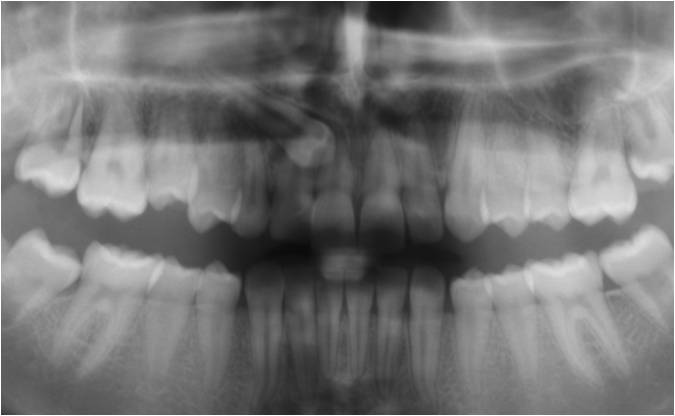

• Panorama viser, om alle tænder er anlagt, og om tandrødder og kæbeled ser normale ud.

• Profilrøntgen giver et billede af, hvordan kæberne er placeret i forhold til hinanden og i forhold til resten af kraniet. Derudover giver det et indtryk af, hvordan væksten vil udfolde sig.

• I nogle tilfælde tages der også et røntgenbillede af hånden, for at se hvor langt dit barn er i sin vækst.

• Der tages røntgenbillede af fortænderne i overkæben som et referencebillede, da disse af og til bliver skadet lidt af en bøjlebehandling. Cirka et halvt år inde i behandlingen bliver der taget ét billede igen som kontrol.

• Alt materiale studeres af en specialtandlæge, der udarbejder en behandlingsplan.